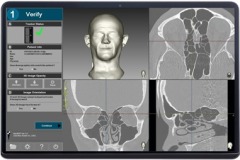

Navient ENT

NaviENT didesain agar tidak menghabiskan banyak menyita banyak tempat di sekitar meja operasi yang sudah sesak. Single Cart, ringkas, langsing, dapat dilipat, dan mudah didorong hingga ke dekat lokasi prosedur. NaviENT juga dengan mudah disimpan sesudah prosedur selesai.

Navient didesain fokus pada hal-hal esensial:

1.Mudah dan segera siap dipakai. SET UP CEPAT HANYA 5 MENIT

2.Akurat, akurasi hingga 0,2 mm

3.Biaya operasional yang sangat rendah. TIDAK MEMERLUKAN CONSUMABLE

4. Instrument dengan permanent marker yang dapat disteril. TIDAK DIPERLUKAN KALIBRASI INSTRUMEN SETIAP KALI PAKAI

5.Hemat ruang.